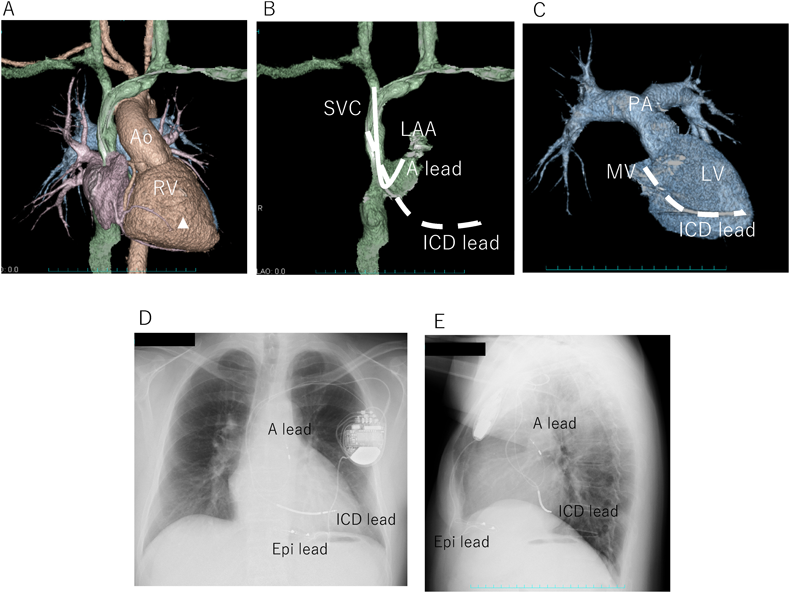

Fig. 1 Complete Epicardial ICD implantation in a patient with asplenia, dextrocardia, single ventricle and ventricular tachycardia at Fontan conversion

A: 3D CT image before Fontan conversion. B: Complete Epicardial ICD implantation at same time of Fontan conversion. Ao, aorta; CT, computed tomography; Epi-A lead, epicardial atrial lead; Epi-ICD lead, ICD lead placed in posterior epicardial space; Epi V lead, epicardial ventricular lead; ICD, implantable cardioverter defibrillator; IVC, inferior vena cava; LSVC, left-sided superior vena cava; RSVC, right-side superior vena cava; SV, single ventricle; SV atrium, systemic venous atrium